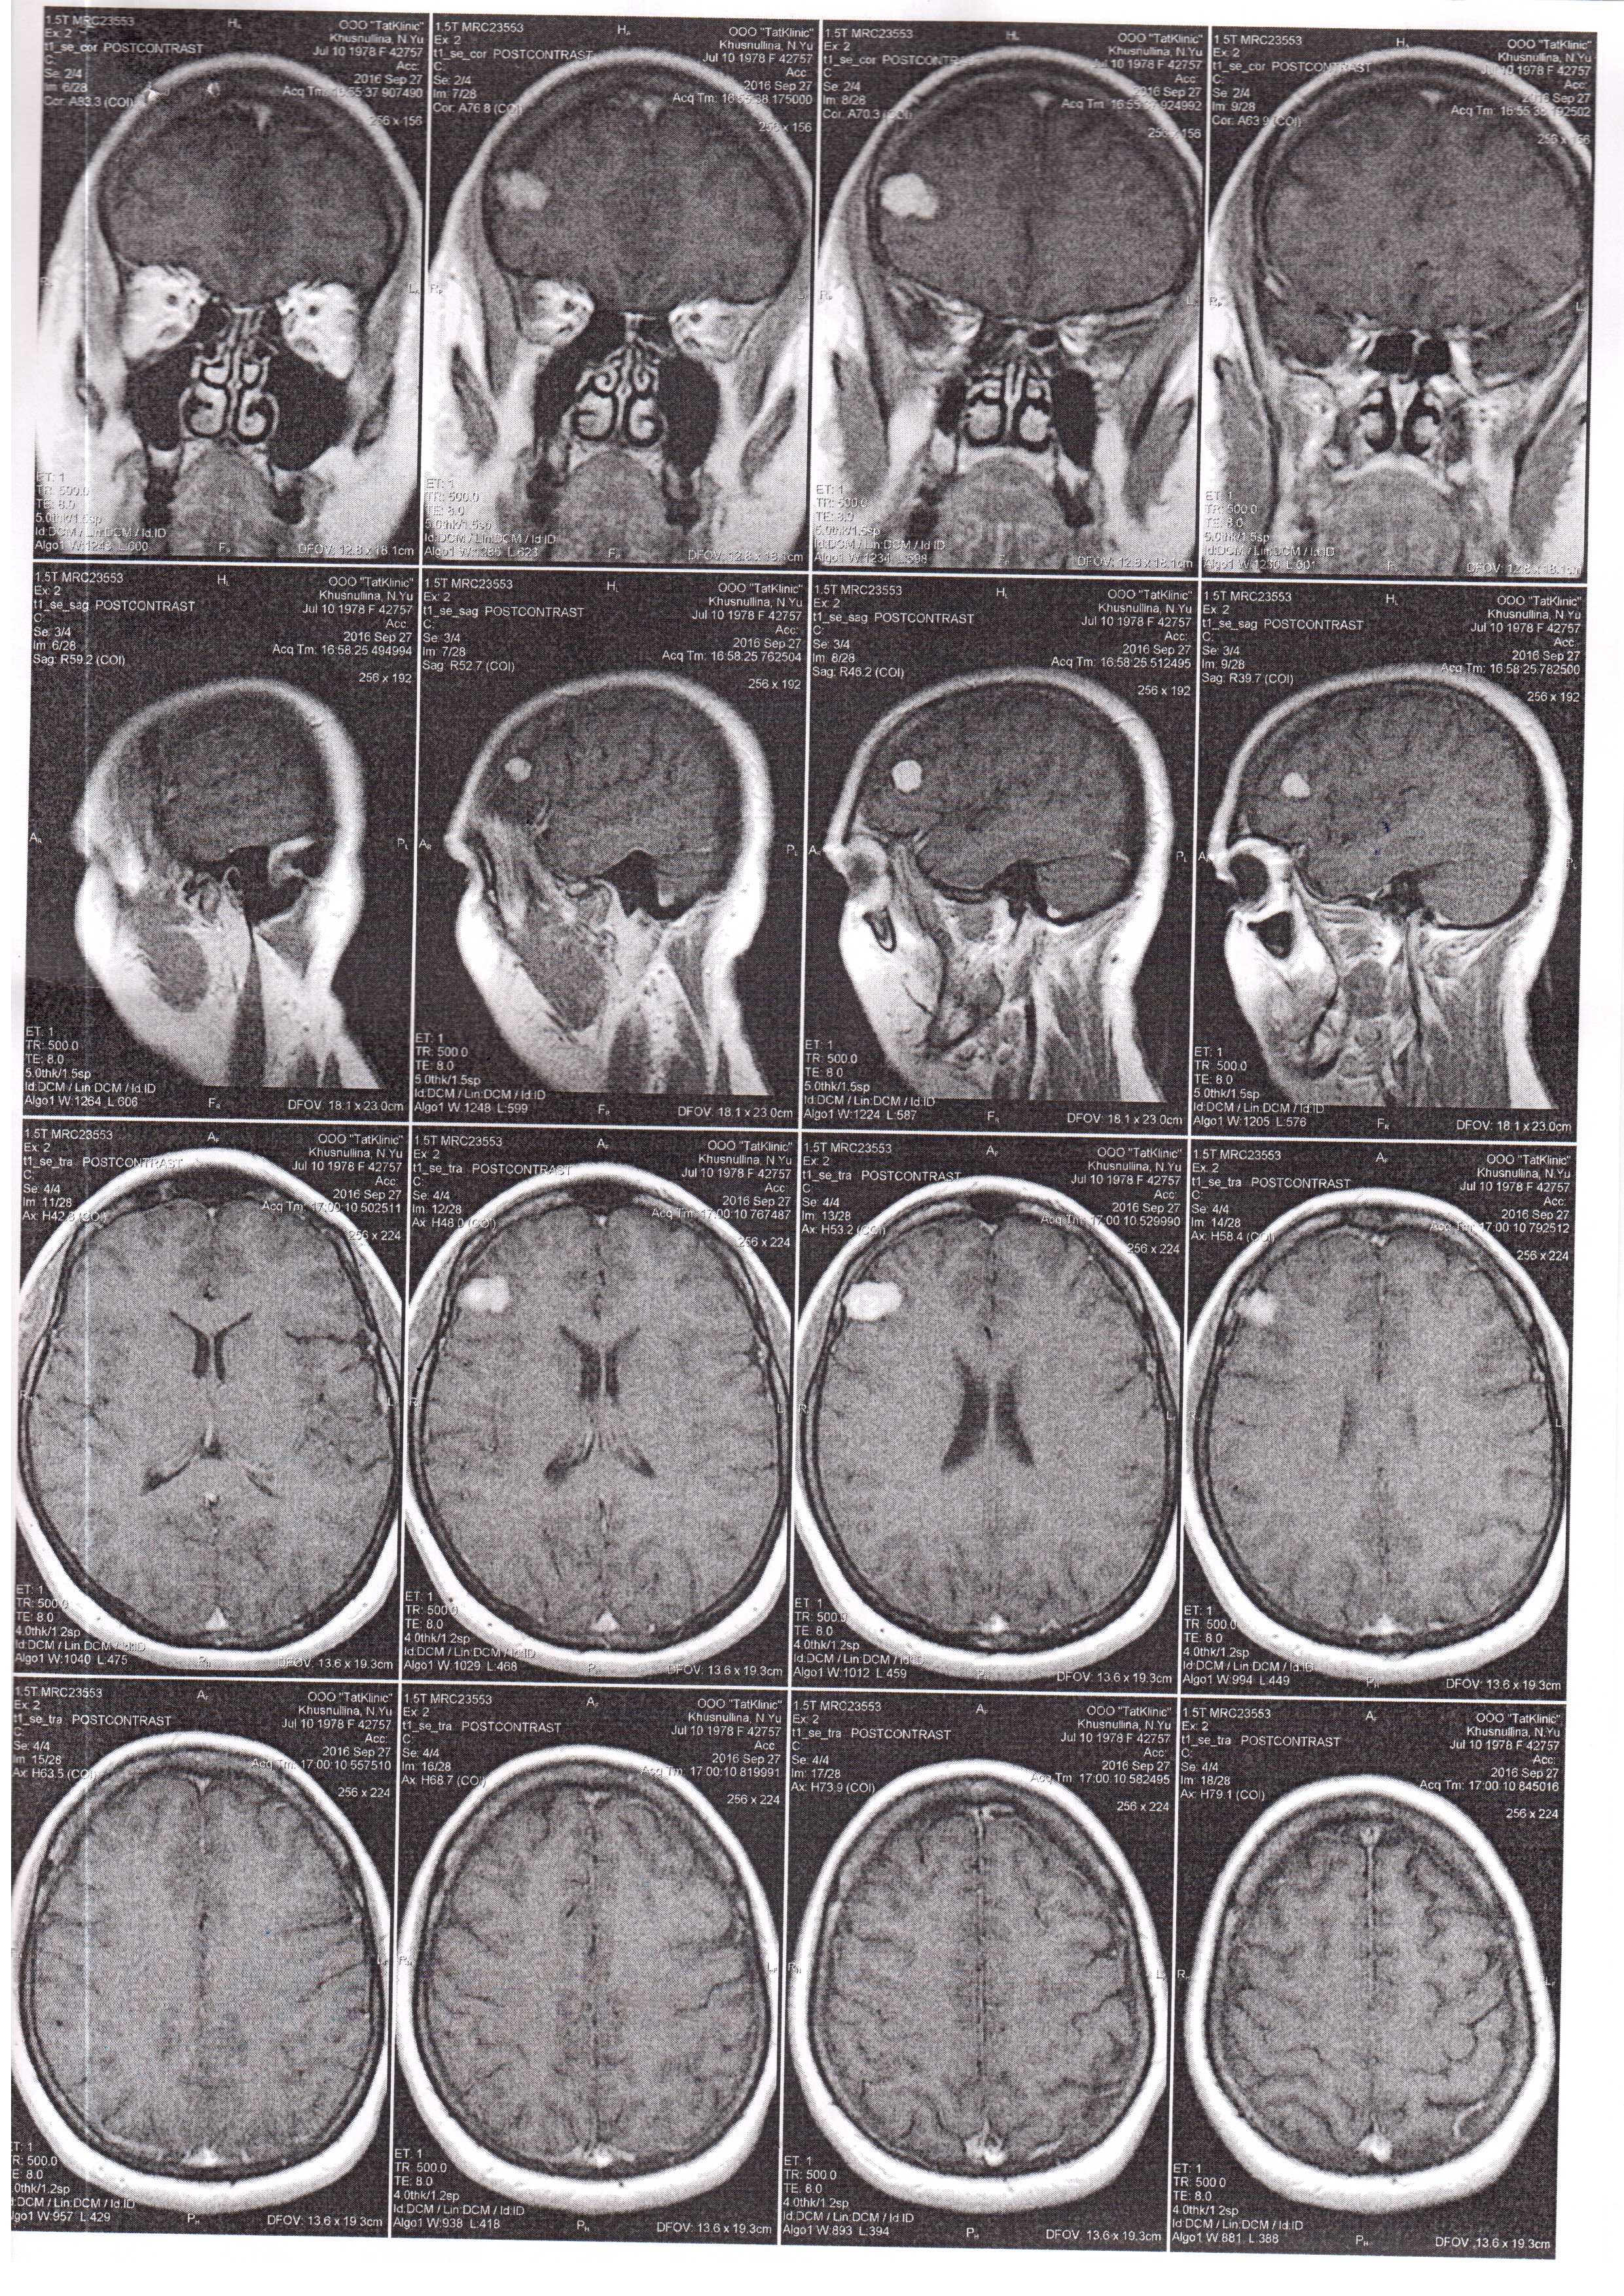

Добрый день! Прошу у Вас совета,что делать с менингиомой. В 2015 году размеры были 17*11*12 мм, а сейчас (МРТ от 27,03,2017 и 27,09,2016) 21*13*15 мм. Нужна ли операция? Или в ней нет пока необходимости.